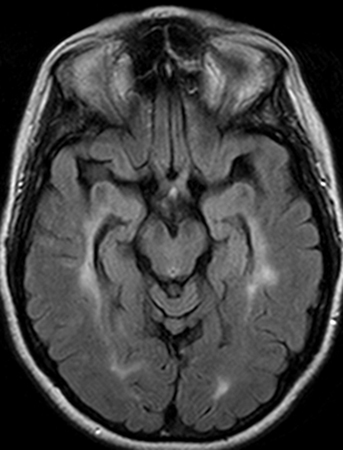

Ressonância nuclear magnética (RNM) transversa mostrando lesões típicas hiperintensas periventriculares da substância branca no parênquima cerebral

Do acervo pessoal de Dra. Cris S. Constantinescu e Dr. Thomas M. Bosley